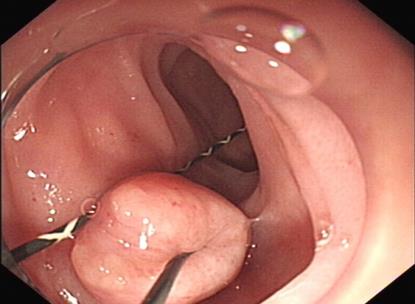

摘要:目的 探讨内镜下电凝切除术与冷切除技术治疗老年复杂性结肠息肉的临床疗效。方法 回顾性分析2021年8月-2023年8月于该院消化内科行内镜下结肠息肉电凝切除和冷切除治疗的100例老年结肠息肉患者的临床资料。根据手术方式的不同,将患者分为电凝组(50例)和冷切组(50例)。统计两组老年结肠息肉患者的息肉切除情况、术中及术后治疗情况、术后疼痛程度、胃肠道生活质量指数(GIQLI)评分、住院时间、治疗总费用,以及随访1年后的复发情况。结果 电凝组共切除息肉108枚,冷切组共切除息肉113枚,冷切组息肉完整切除率高于电凝组,标本受损率低于电凝组,差异均有统计学意义(P < 0.05);两组患者平均息肉切除数量和标本回收率比较,差异均无统计学意义(P > 0.05)。冷切组手术时间和住院时间短于电凝组,治疗总费用少于电凝组,术中钛夹使用率低于电凝组,差异均有统计学意义(P < 0.05)。电凝组术中出血、迟发出血、穿孔和腹痛发生率分别为6.00%、2.00%、2.00%和6.00%,高于冷切组的2.00%、0.00%、0.00%和2.00%,两组患者并发症总发生率比较,差异有统计学意义(P < 0.05)。冷切组术后24和48 h的视觉模拟评分法(VAS)评分低于电凝组,差异均有统计学意义(P < 0.05)。冷切组术后3个月的GIQLI评分高于电凝组,差异有统计学意义(P < 0.05)。冷切组术后1年的复发率低于电凝组,但两组患者比较,差异无统计学意义(P > 0.05)。结论 内镜下冷切除技术治疗老年复杂性结肠息肉患者,临床疗效较电凝切除术好,且安全性高,治疗费用少。值得临床推广应用。